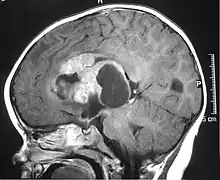

| MRI of an AT/RT | |

Appearance on radiologic exam

AT/RTs can occur at any sites within the CNS; however, about 60% are located in the posterior fossa or cerebellar area. The ASCO study showed 52% posterior fossa; 39% sPNET; 5% pineal; 2% spinal, and 2% multifocal.[3]

The tumors' appearance on CT and MRI are not specific, tending towards large size, calcifications, necrosis (tissue death), and hemorrhage (bleeding). Radiological studies alone cannot identify AT/RT; a pathologist almost always has to evaluate a brain tissue sample.

The increased cellularity of the tumor may make the appearance on an uncontrasted CT to have increased attenuation. Solid parts of the tumor often enhance with contrast MRI finding on T1 and T2 weighted images are variable. Precontrast T2 weighted images may show an isosignal or slightly hypersignal. Solid components of the tumor may enhance with contrast, but not always. MRI studies appear to be more able to pick up metastatic foci in other intracranial locations, as well as intraspinal locations.

Preoperative and follow-up studies are needed to detect metastatic disease.